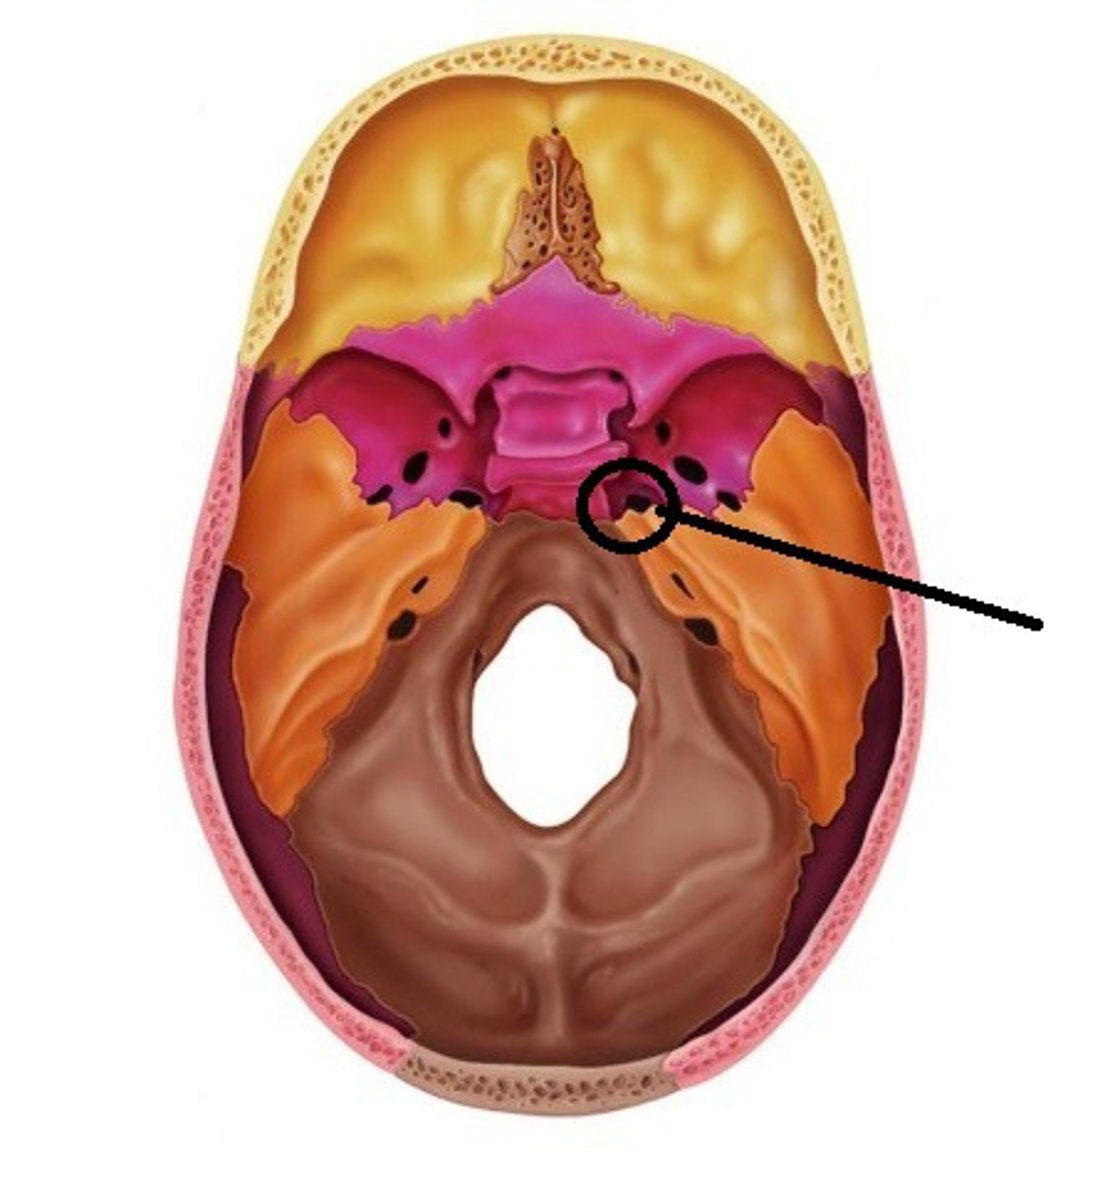

Foramen Lacerum

A triangular hole in the base of the skull located between the sphenoid, apex of petrous temporal and basilar part of occipital

Jugular Foramen

CN IX, X, XI, superior bulb of internal jugular, inferior petrosal and sigmoid sunuses, meningeal branches of ascending pharyngeal and occipital arteries pass through

Foramen Rotundum

Located at the base of the greater wing of the sphenoid, inferior to the superior orbital fissure. It provides a connection between the middle cranial fossa and the pterygopalatine fossa. The maxillary nerve (branch of the trigeminal nerve, CN V) passes through this foramen.

Foramen Spinosum

The middle meningeal artery, middle meningeal vein, and the meningeal branch of the mandibular nerve pass through the foramen.

Foramen Ovale

An oval shaped opening in the middle cranial fossa located at the posterior base of the greater wing of the sphenoid bone. It transmits the mandibular division of the trigeminal nerve (CN V3) and the accessory meningeal artery.